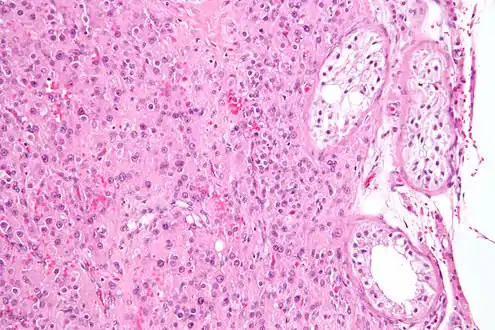

High magnification micrograph of a Leydig cell tumour, H&E stain